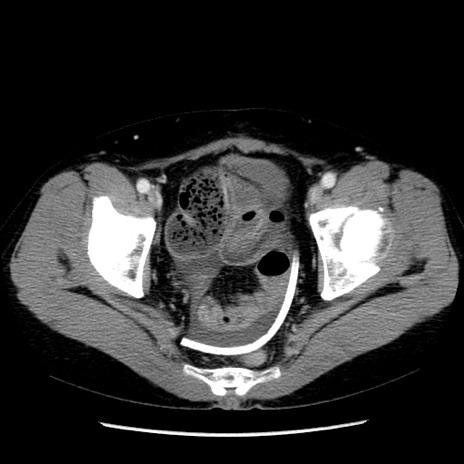

症例6(横断像)

【症例】50歳代女性

【主訴】下腹部痛

【現病歴】本日朝より下痢2回あり。 昼食を食べた後、嘔吐3回、下腹部痛認め、症状軽快せず、当院救急搬送。

【既往歴】卵巣癌術後(8年前に当院で卵巣摘出)

【身体所見】 意識清明、腹部:平坦、腸蠕動音→、やや硬、下腹部自発痛・圧痛あり、反跳痛あり、筋性防御なし。

【データ】WBC 16000、CRP 0.01